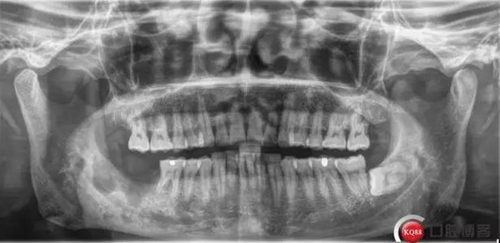

X線及CBCT檢查:47、48根尖周區(qū)大面積低密度影像,波及下牙槽神經(jīng)管,部分區(qū)域至神經(jīng)管以下。CBCT顯示神經(jīng)管走形于47根尖炎癥區(qū)下方(已侵犯)48炎癥區(qū)頰側(cè)(已侵犯)

術(shù)前CBCT分析